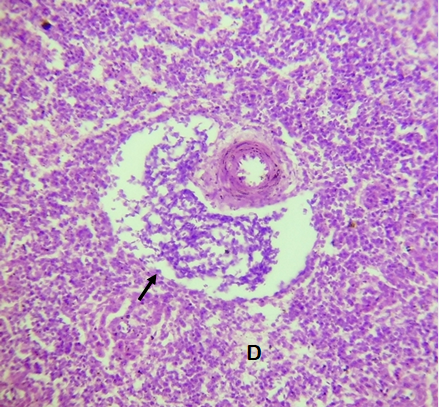

Gross pathology

The gross lesions observed at postmortem were congested comb and wattles (30.00%), prolapsed vent (40.00%) and pale carcasses (100.00%) in addition to pale, friable and ruptured liver (100.00%), cardiomegaly (10.00%) and renomegaly (10.00%). Others were congested spleen (10.00%), congested lungs (100.00%), frothy exudation within the trachea (20.00%), congested and ruptured ovarian follicles (100.00%) and shell-less eggs within the oviduct and/or abdominal cavity (100.00%) as shown in Figure 1.

Figure 1 The abdominal cavity of a pullet diagnosed of mixed bacterial infection on a layer flock in Masaka, Nasarawa State, Nigeria. Note the congested and ruptured ovarian follicles (arrows) and shell-less egg within the abdominal cavity (A).